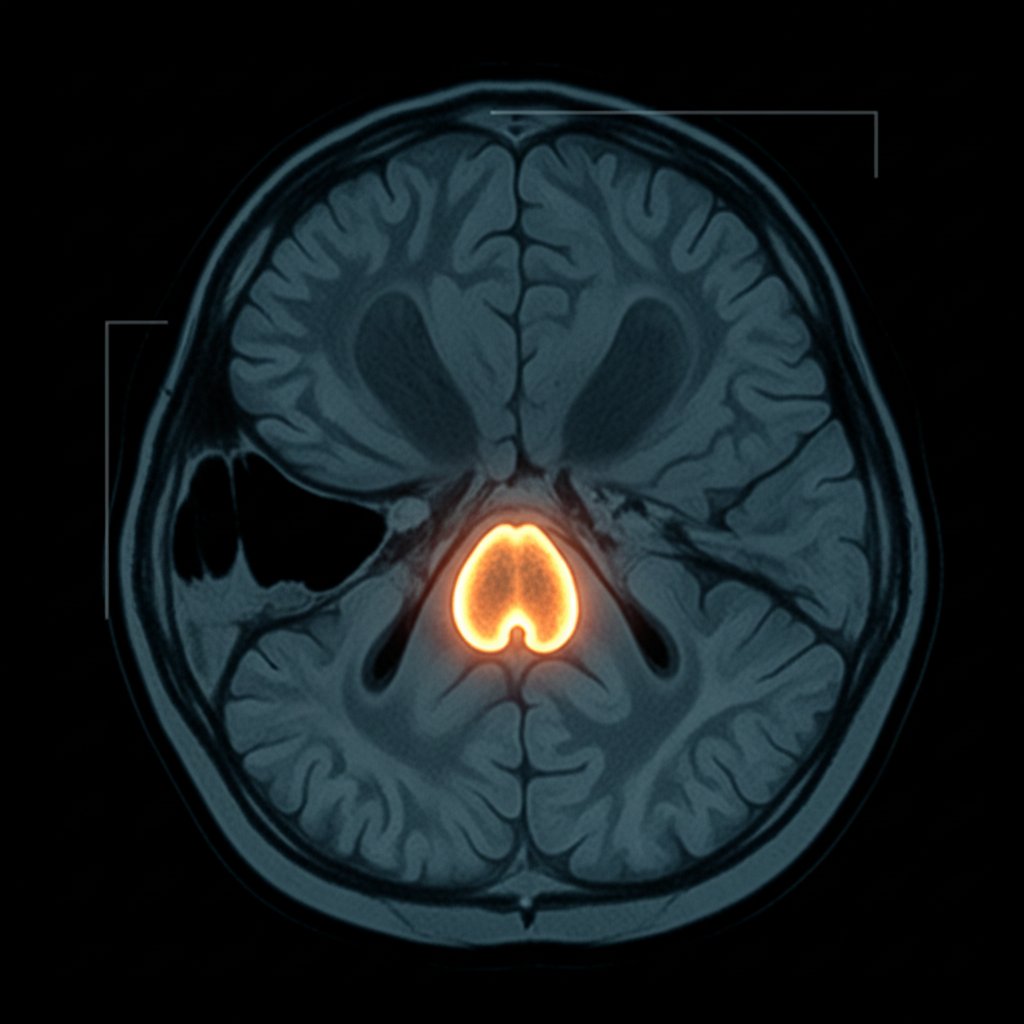

Gdy nadchodzi atak paniki, twoje ciało nie gra według logicznych reguł. W jednej chwili serce zaczyna walić jak oszalałe, oddech płytki, dłonie lepkie od potu. To nie jest wybryk wyobraźni. Neurobiolodzy podkreślają, że atak paniki to efekt efektownych (i przerażających) reakcji chemicznych w mózgu. Podczas paniki ciało migdałowate – niewielka, ale potężna struktura w mózgu – aktywuje się błyskawicznie, wywołując „alarm” na całe ciało. Kortyzol i adrenalina zalewają system, blokując racjonalne myślenie. Nagle ciało przygotowuje się do ucieczki albo walki, mimo że realnego zagrożenia nie ma.